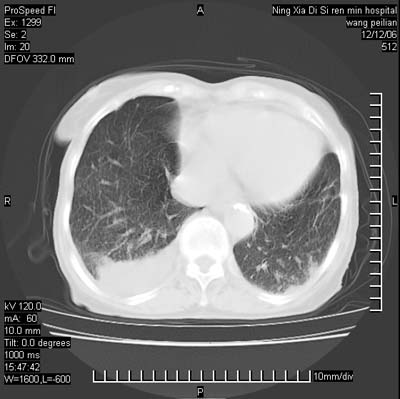

标题: CT5609:胸部:女77 病史不详

两肺可见多个大小不等的结节,左侧有胸水,纵隔淋巴结增大,考虑是细支气管肺泡癌

两肺尖纤维索状影,两下肺结节块状影,且有钙化灶,右胸腔积液。考虑肺结核并胸膜炎。

两肺尖纤维索状影,两下肺结节块状影,且有钙化灶,右胸腔积液。考虑肺结核并胸膜炎肺间质纤维化

考虑:1、慢性支气管炎合并全小叶型肺气肿、间质纤维化;

2、双肺结核;

3、右侧胸膜炎(积液)。

1、双肺继发型肺结核(以纤维、增殖灶为主);

2、右侧胸腔积液;

3、其余符合老年肺改变。

双肺见多个结节状及条索状影,双侧胸腔积液,右侧叶间积液,考虑结核性胸膜炎